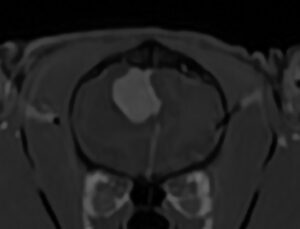

10歳、去勢雄の猫ちゃんで、 1年前からてんかん発作が続いているとのことでした。発作は抗てんかん薬などの内科治療ではコントロールできず、週3~4回発現しているとのことでした。 原因究明のためMRI検査を実施すると、大きな脳腫瘍が認められました。 画像の特徴から髄膜腫が疑われました。

ご家族と相談の結果、できる治療をしてあげたいとのことで、開頭による腫瘍摘出術を実施しました 。病理診断は当初の予測通り、猫の脳腫瘍で最多の髄膜腫でした 。